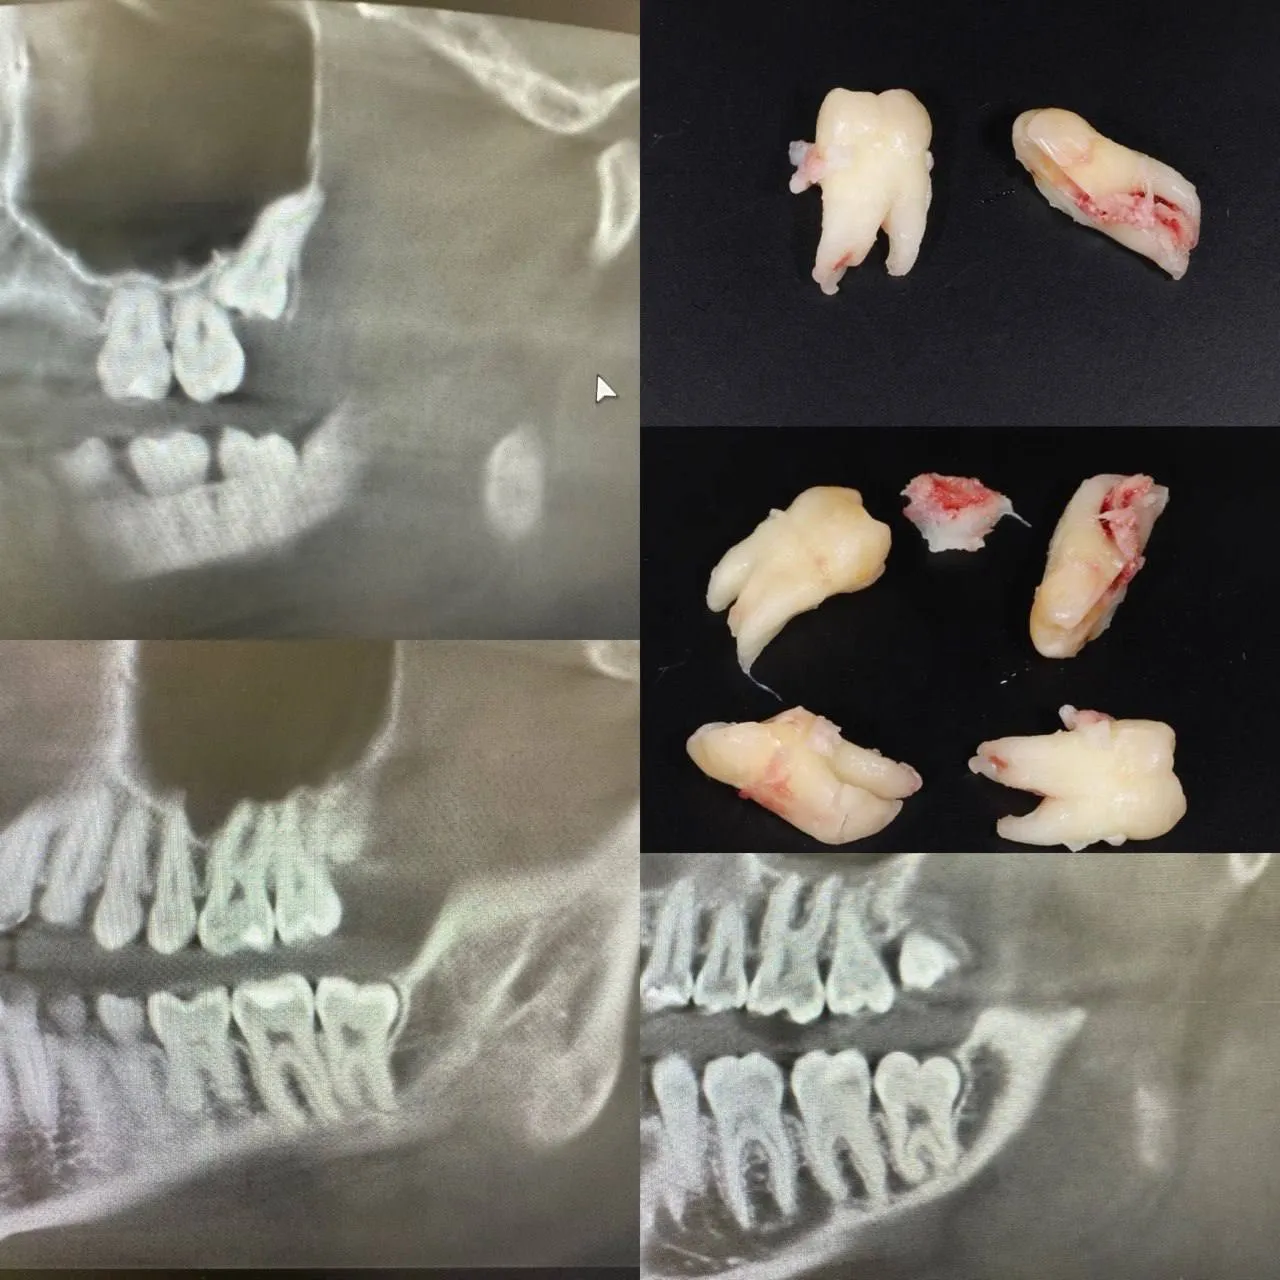

Видалення зубів мудрості у медикаментозному сні

Відкритий синус-ліфтинг

Видалення зуба 3.4 + Імплантація 3.4 3.5 3.7. Формувачі ясен. Система Neobiotech